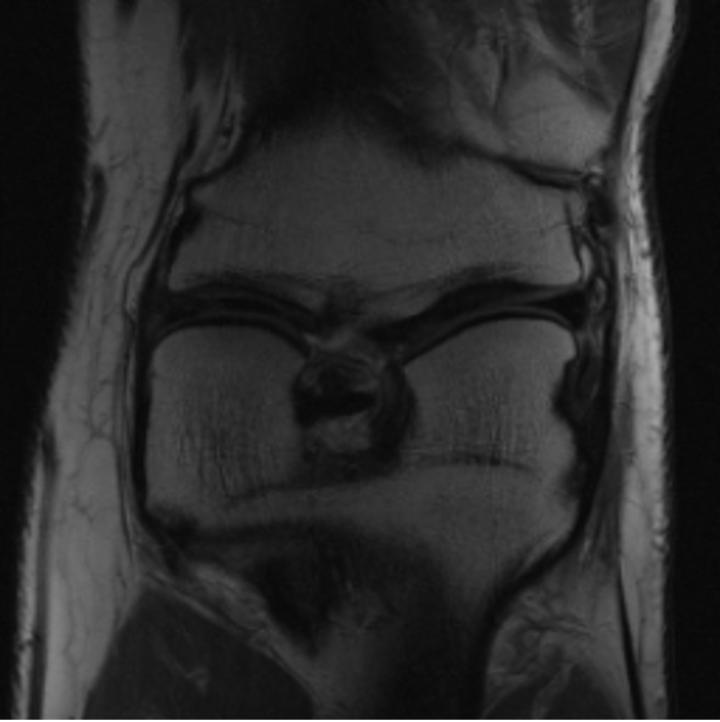

One way to test the generalization capability of the trained X-Diffusion is to test it on a completely different domain from an MRI dataset not seen during training. We report the single-slice results on the test set of knees from NYU fastMRI [33, 80], using the X-Diffusion trained on the BRATS brain MRIs. The test PSNR result is 34.17 and an example is shown in Figure 8. It shows how successfully X-Diffusion can generate knee MRIs (out-of-domain) despite being trained on brains.

Small Knee MRIs clinical study. To qualitatively assess how realistic our generated knee out-of-domain 3D volumes were (produced from a single slice), we gave 20 generated examples alongside their real MRI counterparts to an expert orthopedic surgeon J. F.. He was then asked to identify the real example from a set of 20 MRI pairs. The surgeon correctly identified the real MRI in only 10 out of 20 pairs, could not decide in 3 pairs, and misidentified the generated MRI as real in the remaining 7 pairs. This further validates the generated out-of-domain MRIs.